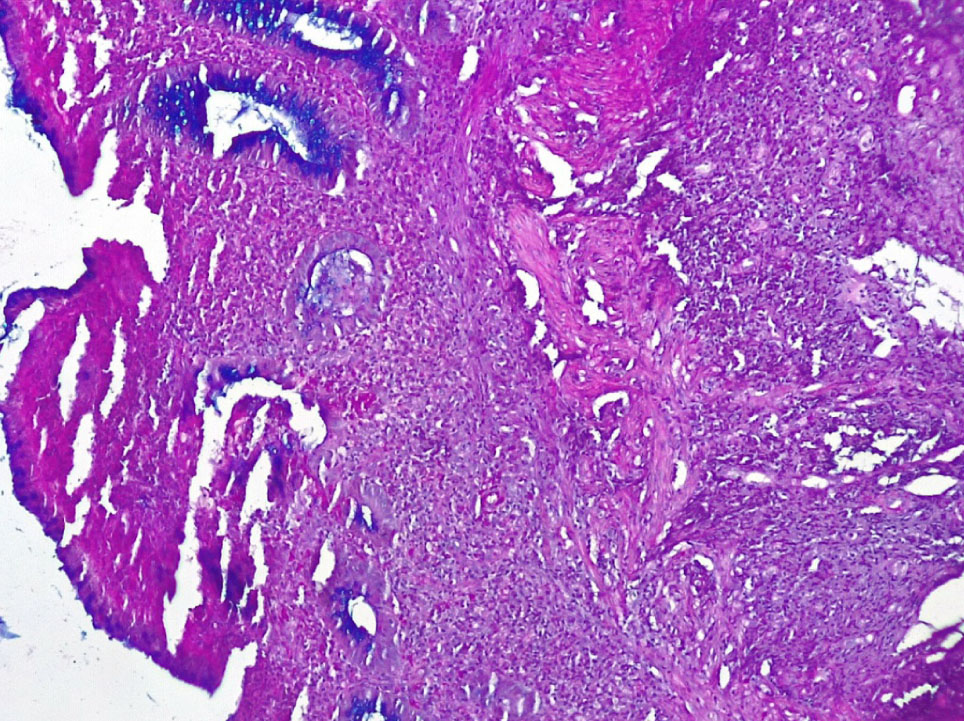

Язвенные дефекты СО толстой кишки были неглубокие и достигали собственную и мышечную пластинки. Вокруг язв отмечалась умеренно или резко выраженная лимфо-плазмоцитарная инфильтрация стромы с примесью нейтрофилов (++, +++), со сдавлением клеточным воспалительным инфильтратом крипт и развитием атрофии цилиндрического эпителия и крипт (++) (рис. 3).